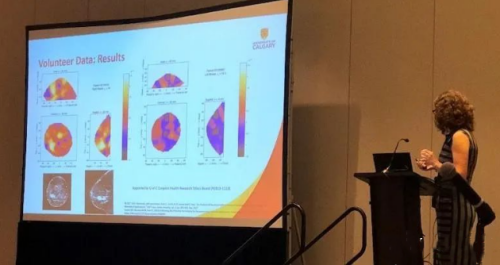

在更小的方面(至少比冰山小),雷达也被用作医疗保健应用的诊断工具,由Elise Fear 博士领导的卡尔加里大学的研究人员旨在检测和监测乳房肿瘤. Fear 博士在 RadarConf 2023 上展示了她的团队的工作,并强调了雷达使其成为有效医疗工具的关键特性。

当涉及鲁棒成像时,通常需要多个接收器来提供足够的空间分集以形成图像。这通常会增加系统的尺寸和成本,并降低患者成像过程的舒适度——例如,在 MRI 期间保持静止。

另一方面,雷达牺牲了分辨率以换取报告的患者舒适度的巨大飞跃,这使得基于雷达的成像成为可能不需要超精细分辨率的首次通过诊断的良好候选者。

成功成像的另一个关键指标是一致性。正如 Fear 博士在她的演讲中所说,“这些应用程序依赖于我们收集一致数据的能力。所以,如果我现在、两周后或一个月后对患者进行扫描,我得到的是相同的照片还是完全不同的东西?”

虽然雷达可能没有其他成像方法的分辨率,但雷达成像在诊断中的一致性肯定不缺乏,据报道结果与患者病史和其他成像机制保持一致。

因此,虽然雷达成像在短期内取代基于辐射的成像可能不现实,但为医疗专业人员添加一种新的、舒适的工具肯定对所有人都有好处,并说明了雷达几乎可以用于任何领域传感应用。